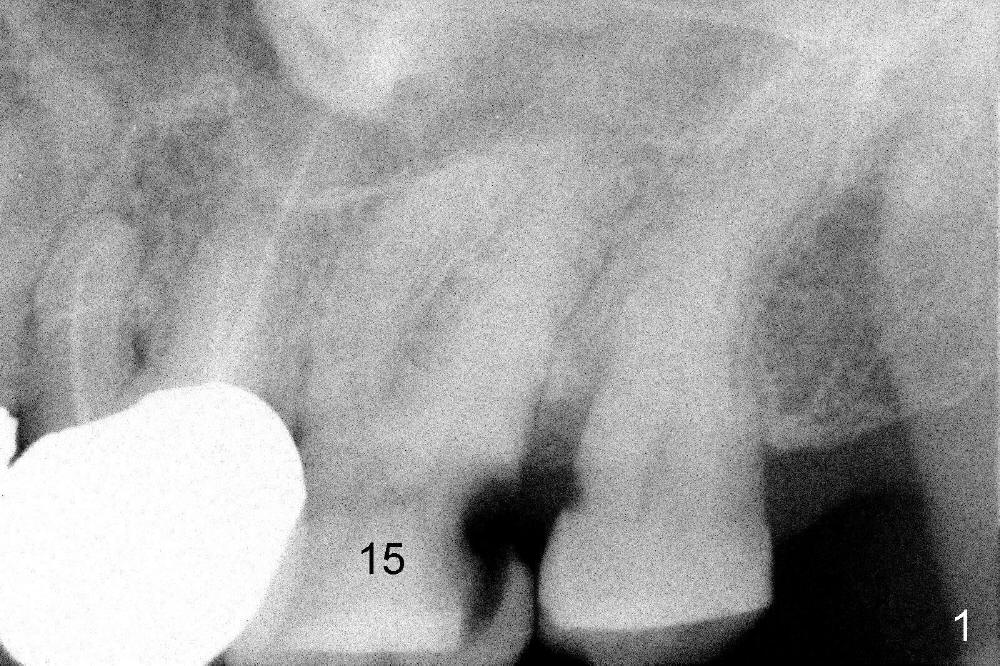

A 66-year-old lady requests restoring a broken tooth (Fig.1). Osteotomy is initiated in a thin septum (Fig.2 (occlusal mirror view) S) by sectioning, drilling and tapping (Fig.3 T). When 7x17 mm tap is removed, the osteotomy is found to form basically in the middle of socket (Fig.4 O). The apical portion of three sockets (Fig.5: MB, P and DB (not labeled) is packed with mixture of autogenous bone and allograft. When a 7x14 mm implant is placed, there are buccal and lingual gaps (Fig.6 *). The latter are bone grafted again (Fig.8 *) and require a coverage. After placement of a 4x3 mm abutment (Fig.7,8 A), an immediate provisional is fabricated (Fig.9 tissue surface view) to cover the remaining sockets (Fig.10 (occlusal mirror view), 11 (buccal view)). The provisional is infra-occlusal, i.e., load-free (Fig.11). The buccal and lingual aspects of the socket are covered by fresh epithelium 8 days postop (Fig.12 <). The implant appears to have osteointegrated 4 months postop (Fig.13). The tooth #16 appears to have shifted mesially. It is difficult to prepare for #15 crown. Luckily the patient agrees to have it extracted because of persistent sensitivity after MO composite. The definitive crown at the site of #15 is cemented 6 months postop (Fig.14).